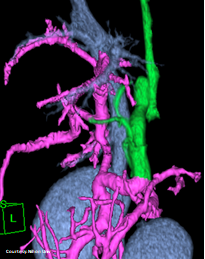

Does the GASTROSPLENIC VEIN (GSV) enter the PORTAL VEIN (PV)?

(Absent GSV)

Does the GASTROSPLENIC VEIN (GSV) enter the CAUDAL VENA CAVA (CdVC) directly?

“LGC +PancV -GSV” Left Gastro-Caval Shunt with Pancreatic Vein contribution and absent Gastro-splenic vein (GSV does not enter PV)

Courtesy: Nihon Univ